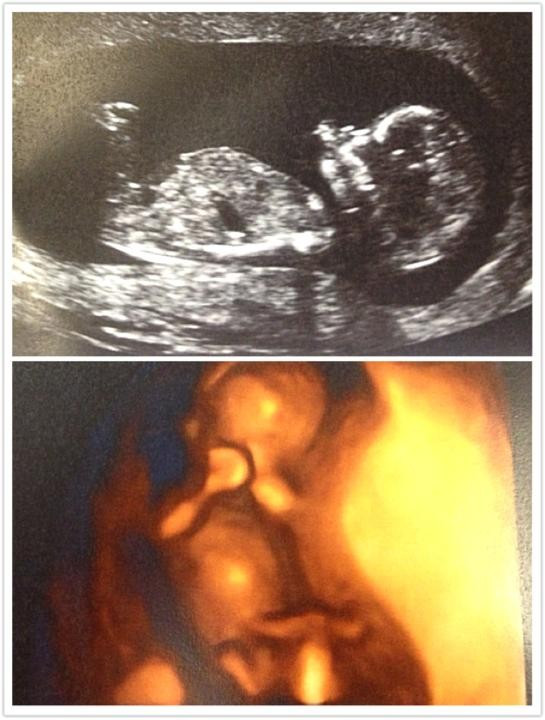

한국이었으면 임신에 대한 축하를 이미 한껏 받고, 임신했다는 사실에 이미 어느 정도 적응한 후 안정기에 접어드는 시기가 12주인데, 우리 부부는 12주에 처음으로 아기를 만나러 산부인과에 갔다. 호주에 와서 처음으로 방문하는 큰 규모의 종합병원 방문에 약간 긴장된 마음으로 남편과 함께 초음파실에 입실하여 각도가 조절되는 침대에 비스듬히 누워 모니터 화면을 응시했다. 산부인과 영상의학과 직원 분이 초음파기기를 준비시켰다. 과연 이 안에 생명체가 있긴 있을까 싶은, 겉보기엔 임신한 티가 전혀 나지 않는 내 배를 직원 분이 이리저리 누르니 이내 화면에 우리 아기가 나타났다!

KakaoTalk_20201006_104102523.jpg 호주에서는 첫 초음파가 12주 차에 진행. 임신 후 처음으로 본 우리 아기.

친구들 SNS에 올라온 사진들에서 다 작은 점이나 젤리곰 같은 모양을 한 태아들만 보았는데 우리 아기는 팔도 있고 다리도 있고 엄청 활발하게 움직이고 있었다. 호주에 있는 베트남 식당이나 일본 식당에 가면 전시되어 있는 복을 부른다는 고양이 인형처럼 한쪽 팔만 위아래로 계속 흔들고 있었는데 우리 남편은 아기가 우리에게 '헬로'라고 인사한다며 설레발치고 있었다.